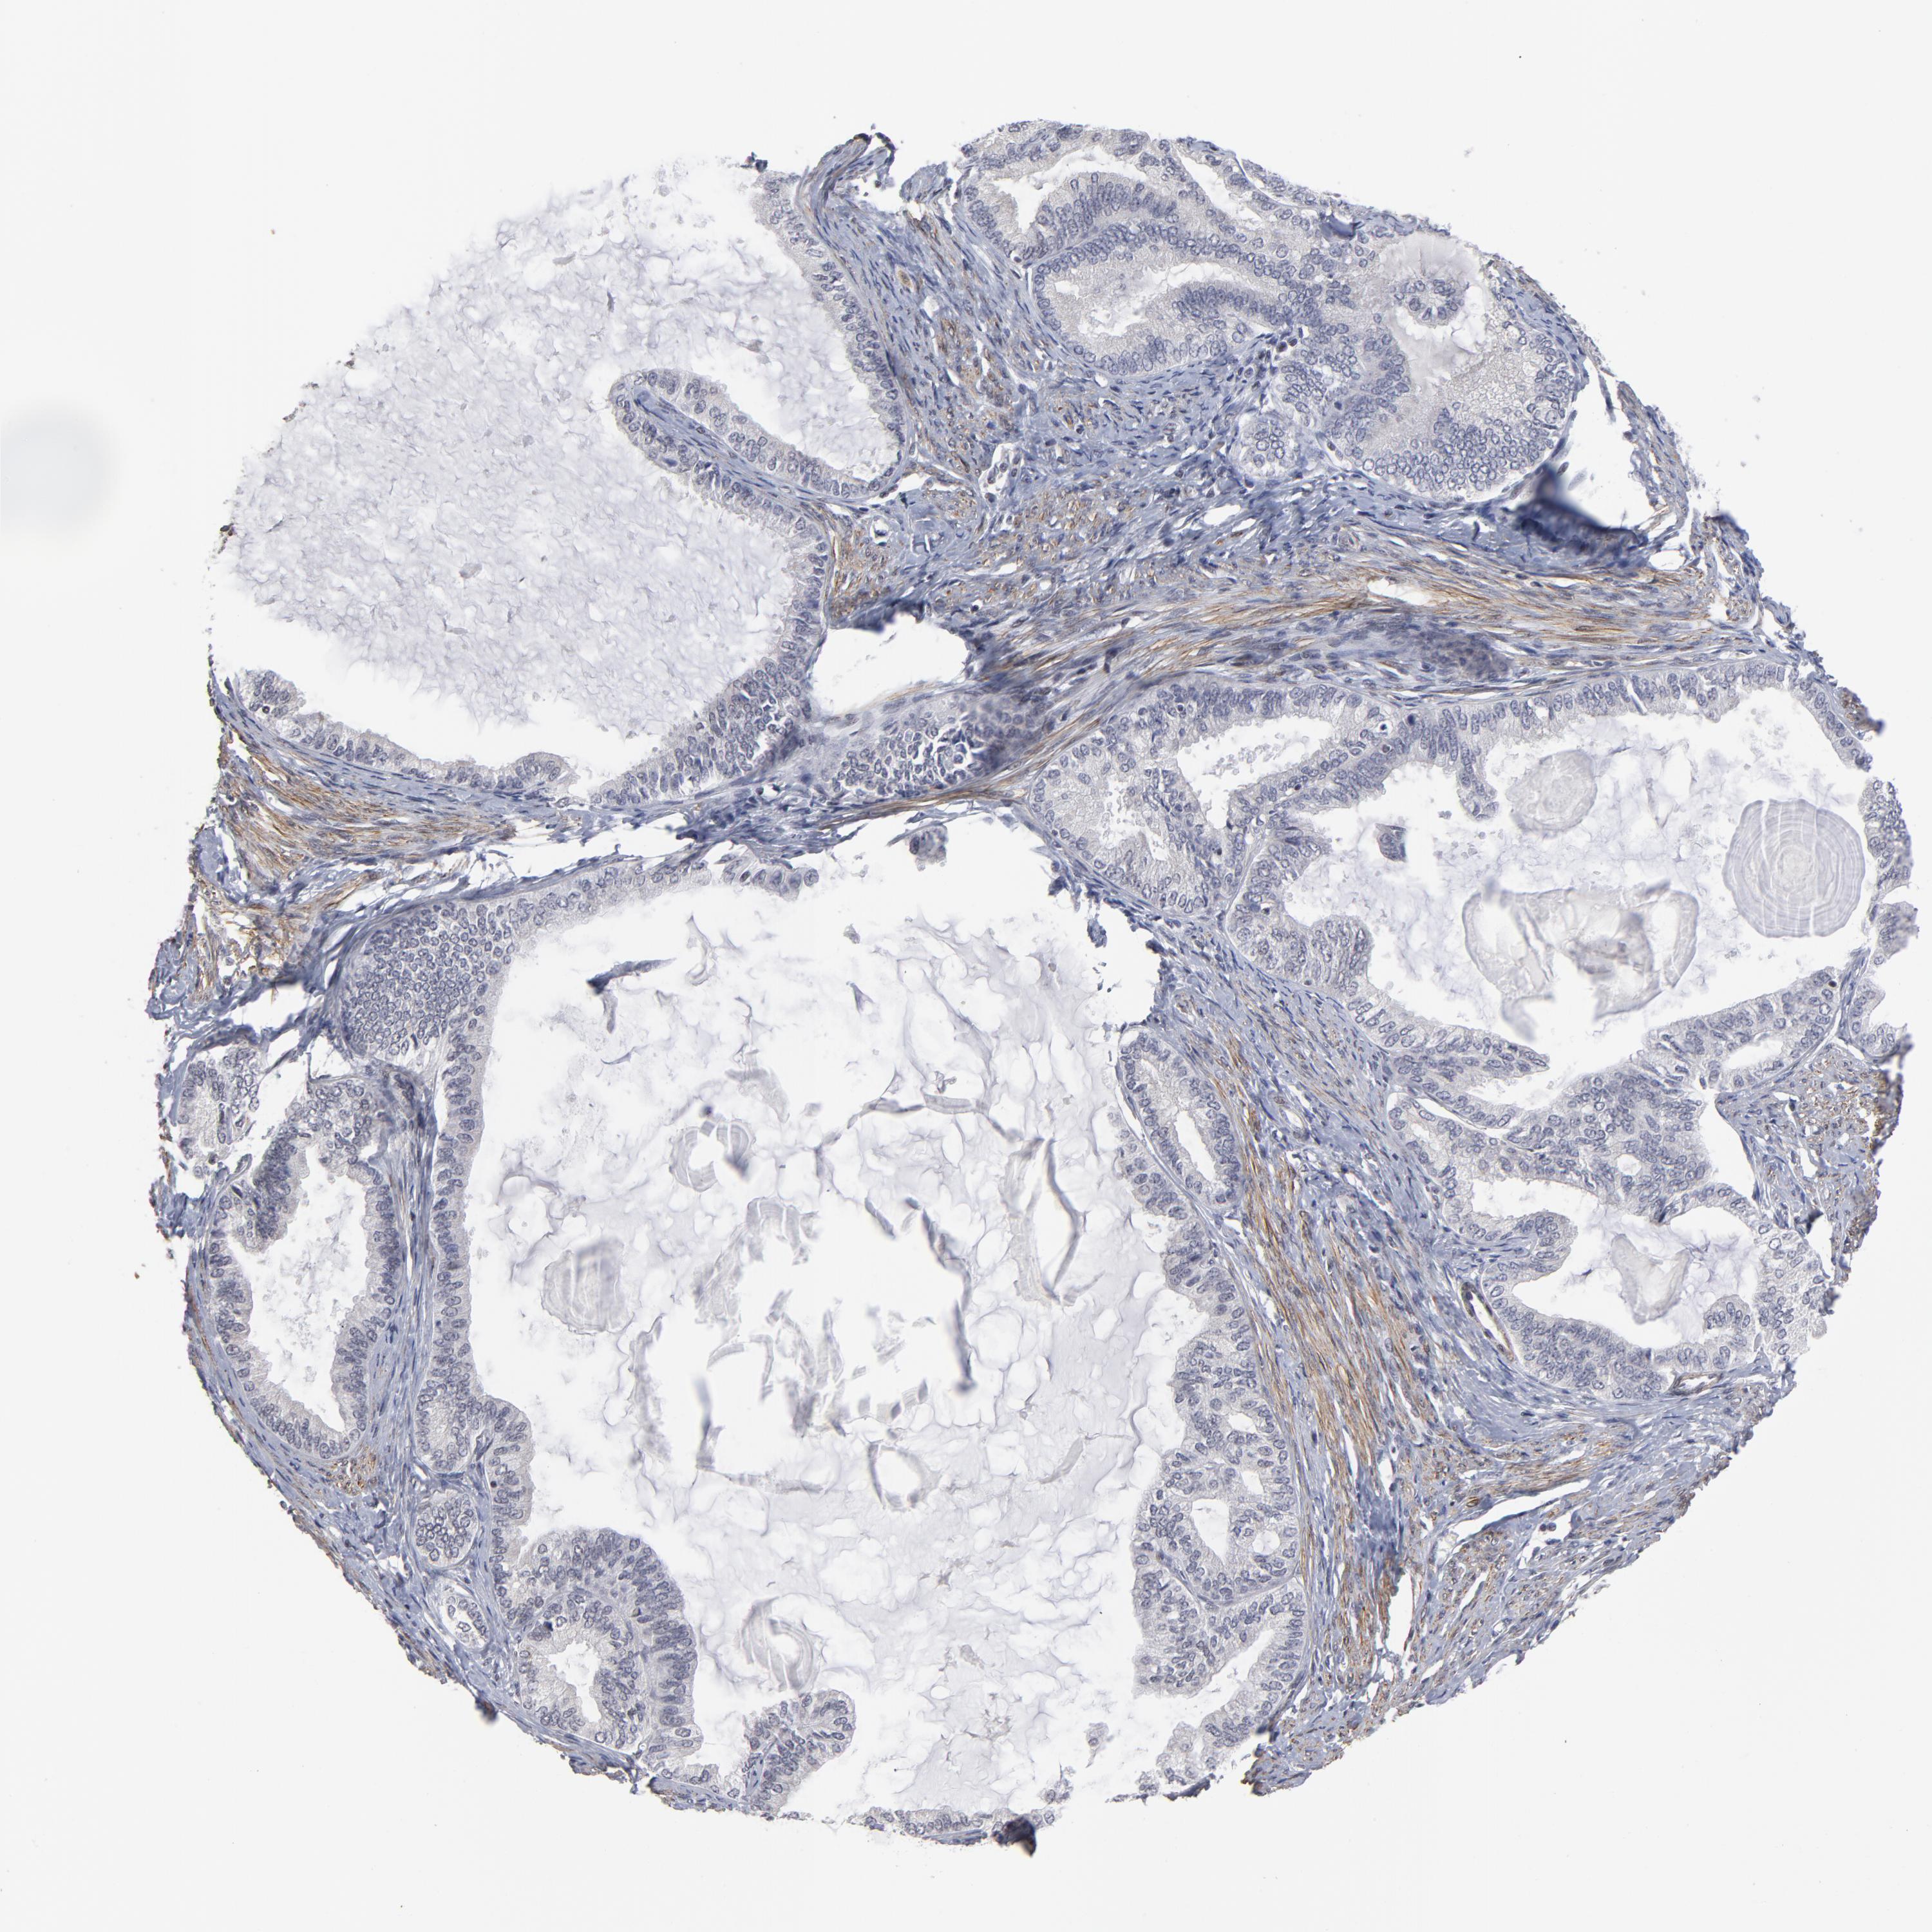

ENDOMETRIAL CANCER - Protein expressioni

A mouse-over function shows sample information and annotation data. Click on an image to view it in a full screen mode. Samples can be filtered based on level of antibody staining by selecting one or several of the following categories: high, medium, low and not detected. The assay and annotation is described here.

Note that samples used for immunohistochemistry by the Human Protein Atlas do not correspond to samples in the TCGA dataset.

Antibody stainingi

Antibody staining in the annotated cell types in the current human tissue is reported as not detected, low, medium, or high, based on conventional immunohistochemistry profiling in selected tissues. This score is based on the combination of the staining intensity and fraction of stained cells.

Each image is clickable and will lead to virtual microscopy that enables deeper exploration of all samples and also displays staining intensity scores, fraction scores and subcellular localization as well as patient and tissue information for each sample.

Antibody HPA004122

Antibody CAB062550

Antibody CAB068181

Antibody CAB068182